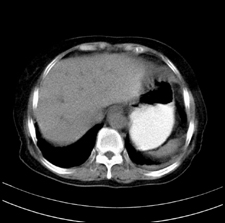

患者,女,75岁。腹痛,体黄5日,膝胸位时腹痛缓解。肝功能明日出来。彩超提示胆总管占位,未见血流信号。心电图提示s-t段改变。患者体质较弱,未能增强。

胆总管上段,腔内有软组织密度影 ,ct值36-44hu。大家看有没有胆管癌的可能。

2楼所说胰腺内钙化不像,象脾脏血管的钙化

典型胆总管多发结石;增强扫描前后ct值是否发生改变是鉴别结石与占位的依据。

典型的胆总管多发结石。在没有增强的情况下,暂不考虑其他。

胆管没有鼠尾征,还是考虑结石